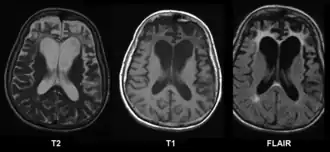

МРТ при болезни Пика | |

При гистологическом исследовании ткани головного мозга в нейронах обнаруживаются необычные включения. Пирамидные нейроны набухшие, содержат цитоплазматические тельца Пика. Толщина серого вещества снижена, граница между серым и белым веществом размыта. Отмечается расширение желудочков (преимущественно передних рогов боковых желудочков) и субарахноидального пространства, углубление борозд полушарий.